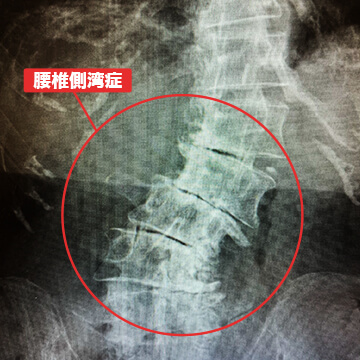

- 腰椎側湾症

腰椎側弯症とは、椎間板や椎間関節の老化によって腰椎が10度以上左右に曲がることを言います。主に腰痛や足の痛みが出現し、側弯が進むと真っ直ぐ立っていても体の左右差が現れます。進行が進むと背骨をボルトで固定する脊椎固定術を選択されることもあります。